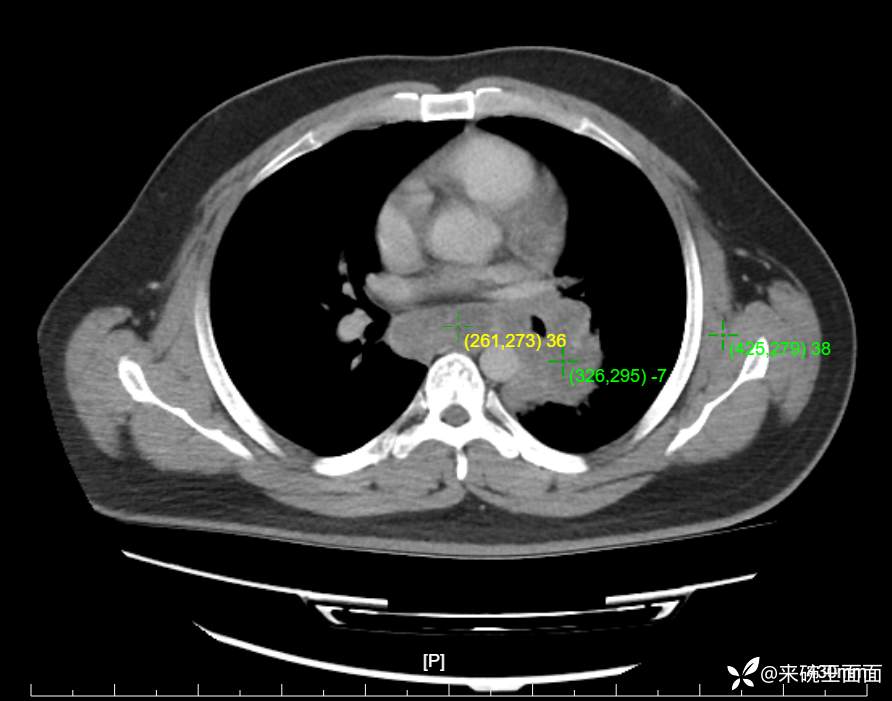

性别:男

年龄:27岁

主诉:胸闷胸痛数月余,休息后可自行缓解,无咯血症状。

个人史:数年吸烟史,具体不详。